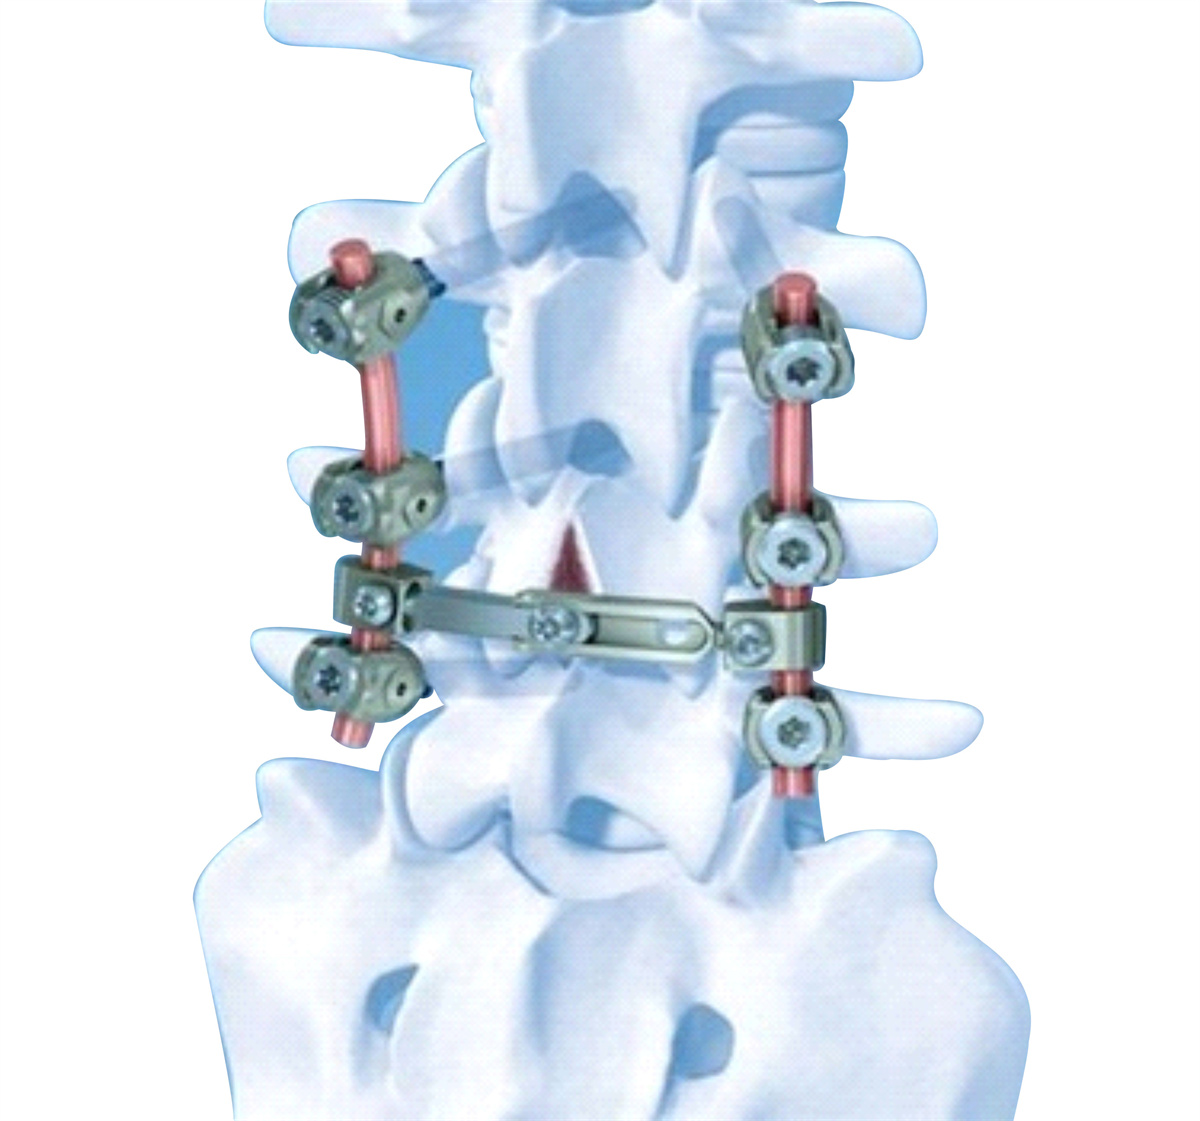

医用不锈钢包括医用不锈钢金属材料和医疗器械用钢。医用不锈钢具有较高的抗拉强度、抗弯曲疲劳强度、良好的韧性、优异的加工性能和耐腐蚀性能等。在医学应用中主要作为承力材料,可用于人体器官,外科骨骼、关节修复,理疗康复,诊断和治疗疾患,并对人体组织无不良影响。

●应用领域︰产品主要用于制作各种手术钳、止血钳、手术刀等,00Cr18Ni14Mo3钢种可用于人体植入,实现进口替代。

| 奥氏体型 | 00Cr18Ni14Mo3 | 医疗上主要人体植入钢板、螺钉等。同时也用于造纸、印染设备,石油化工及耐有机酸腐蚀的装备等。 |